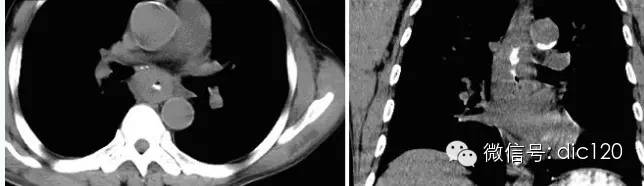

【影像表現】 CT:表現現為食管壁明顯增厚,管腔狹窄;食管與周圍結構分界不清食管吞鋇:食管中段充盈缺損,管腔不規則狹窄,管壁僵硬,粘膜糾集破壞,與正常食管壁分界清晰。

【診斷】 病理診斷:食管(中下段)高-中分化鱗狀細胞癌,侵及食管壁全層。(圖1.2)

影像學診斷要點:內鏡檢查并活檢是診斷食管癌首選的方法。內鏡下食管粘膜染色有助于提高早期食管癌的檢出率。X線檢查:早期食管癌:病變區黏膜皺襞增粗紊亂,中斷及扭曲;小凹陷或隆起性病變,直徑約<5mm,管壁輕度僵硬,擴張伸展稍受限。可形成潰瘍,呈地圖狀。病變常累及周徑于局部,與正常管徑分界截然。進展期:蕈傘型:管腔內菜花樣或蕈傘樣充盈缺損,偏于食管一側,范圍較大,可見不同程度梗阻。潰瘍型:縱形腔外龕影,龕影可見尖角征,周邊可見環堤(周圍腫瘤組織呈帶狀密度減低區)。浸潤型:局限性環形狹窄,輪廓毛糙,與正常食管分界清楚,鋇劑通過緩慢,近端不同程度擴張。髓質型:廣泛侵犯食管全層,形成腔外腫物,管腔狹窄,表面可見潰瘍。混合型:以上多種表現均可存在。CT:食管壁環形或不規則增厚,厚度>5mm應視為異常;或形成腔內腫塊,多為廣基底,表面有時可見龕影;食管周圍脂肪層模糊、消失;周圍器官受累或(和)淋巴結轉移;增強掃描可見腫塊輕度強化,較大瘤體強化不均勻,可合并低密度壞死灶。MRI:掃描前需囑咐病人吞服適量液體。中晚期食管癌表現為信號異常,T1WI與肌肉信號近似,T2WI較肌肉信號高,增強掃描病灶明顯強化。